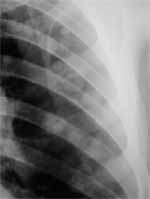

Figura 3. Carcinoma de célula pequeña parahiliar derecho.

Dentro de las características clínicas de este tipo de tumor se encuentran la gran proporción de síndromes paraneoplásicos asociados a éstos, como son el de Eaton-Lambert (17), secreción inadecuada de hormona antidiurética, síndrome de Cushing y otros (23). Dentro de la sintomatología general se pueden presentar síntomas constitucionales (23).